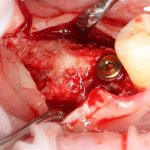

Итак, Зинаида на приеме.

Вот клиническая картина через 4 месяца после ранее проведенной имплантации с остеопластикой:

Как видишь, коллеги из недалекой дружественной страны не осилили снятие швов. Мне это не нравится, хотя и объясняет, почему люди готовы ехать за тыщи километров ради 20-минутной операции удаления зуба мудрости.

Ну хорошо. Швы сняли. Делаем разрез. Обрати внимание, что после всех проведенных операций у нас остается очень небольшой по ширине слой жевательной слизистой оболочки: